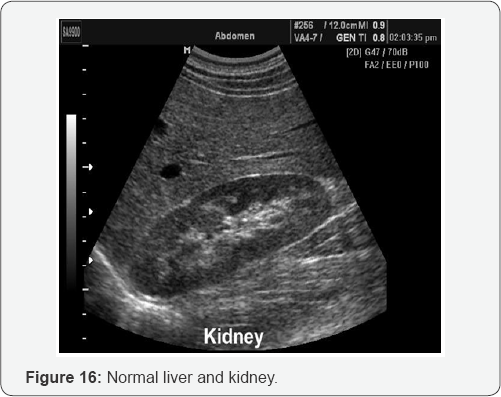

PV dilation due to obstruction. Reverse flow to SMV, IMV, and SV. Blood that cannot enter into PV must return to systematic circulation via anatomotic sites. Results: Esophageal varices, rectal hemorrhoids, caput medusa, etc (Figure 15-29).

B. Sonographic characteristics of cirrhosis:

a. Hyper echoic liver

b. Course texture.

c. Irregular/nodular surface.

d. Small liver

e. Caudate lobe hypertrophy and decrease echogenicity.

f. Non visualization of hepatic veins.

g. Portal vein dilation >13mm.

h. Portal vein reverses flow.

i. Portal vein hypertension.

j. Dilation of splenic veins, SMV, IMV with reverse flow

k. Splenomegaly.

l. Ascites.